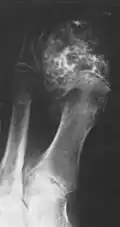

Ein Chondrosarkom ist ein maligner Knochentumor, dessen Zellen Knorpelmatrix, jedoch im Gegensatz zum Osteosarkom keine Knochensubstanz (Osteoid) bilden. Anders als das Chondrom weist das Chondrosarkom ein größeres Zellreichtum, Pleomorphie und Kernatypien auf.[1]

Das Chondrosarkom ist der zweithäufigste bösartige Knochentumor. Sein Auftreten nimmt mit dem Alter zu und erreicht um das 6. Lebensjahrzehnt seinen Gipfel. Es sind mehr Männer als Frauen betroffen. Bevorzugt tritt der Tumor in den Beckenknochen und am rumpfnahen Femur auf.[1]